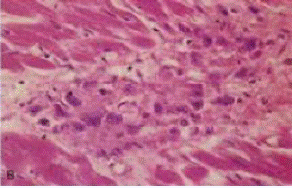

lesioni cardiache sono i corpi di Aschoff. Essi sono formati da aree di

necrosi fibrinoide, circondati da linfociti, macrofagi, occasionali

plasmacellule ed istiociti rigonfi

attivati, chiamati cellule di Anitschkow e di Aschoff.

CELLULE DI ANITSCHKOW E DI ASCHOFF: sono patognomiche per la

malattia. Hanno un citoplasma abbondante amfofilo, nucleo centrale e rotondo,

cromatina disposta a nastro ondulato, da questo il nome di cellule "a forma di bruco"

Le cellule più grandi multinucleate prendono il nome di cellule di Aschoff. Esse si

repertano sia nel pericardio che nell'endocardio. In tal caso si parla di pancardite.